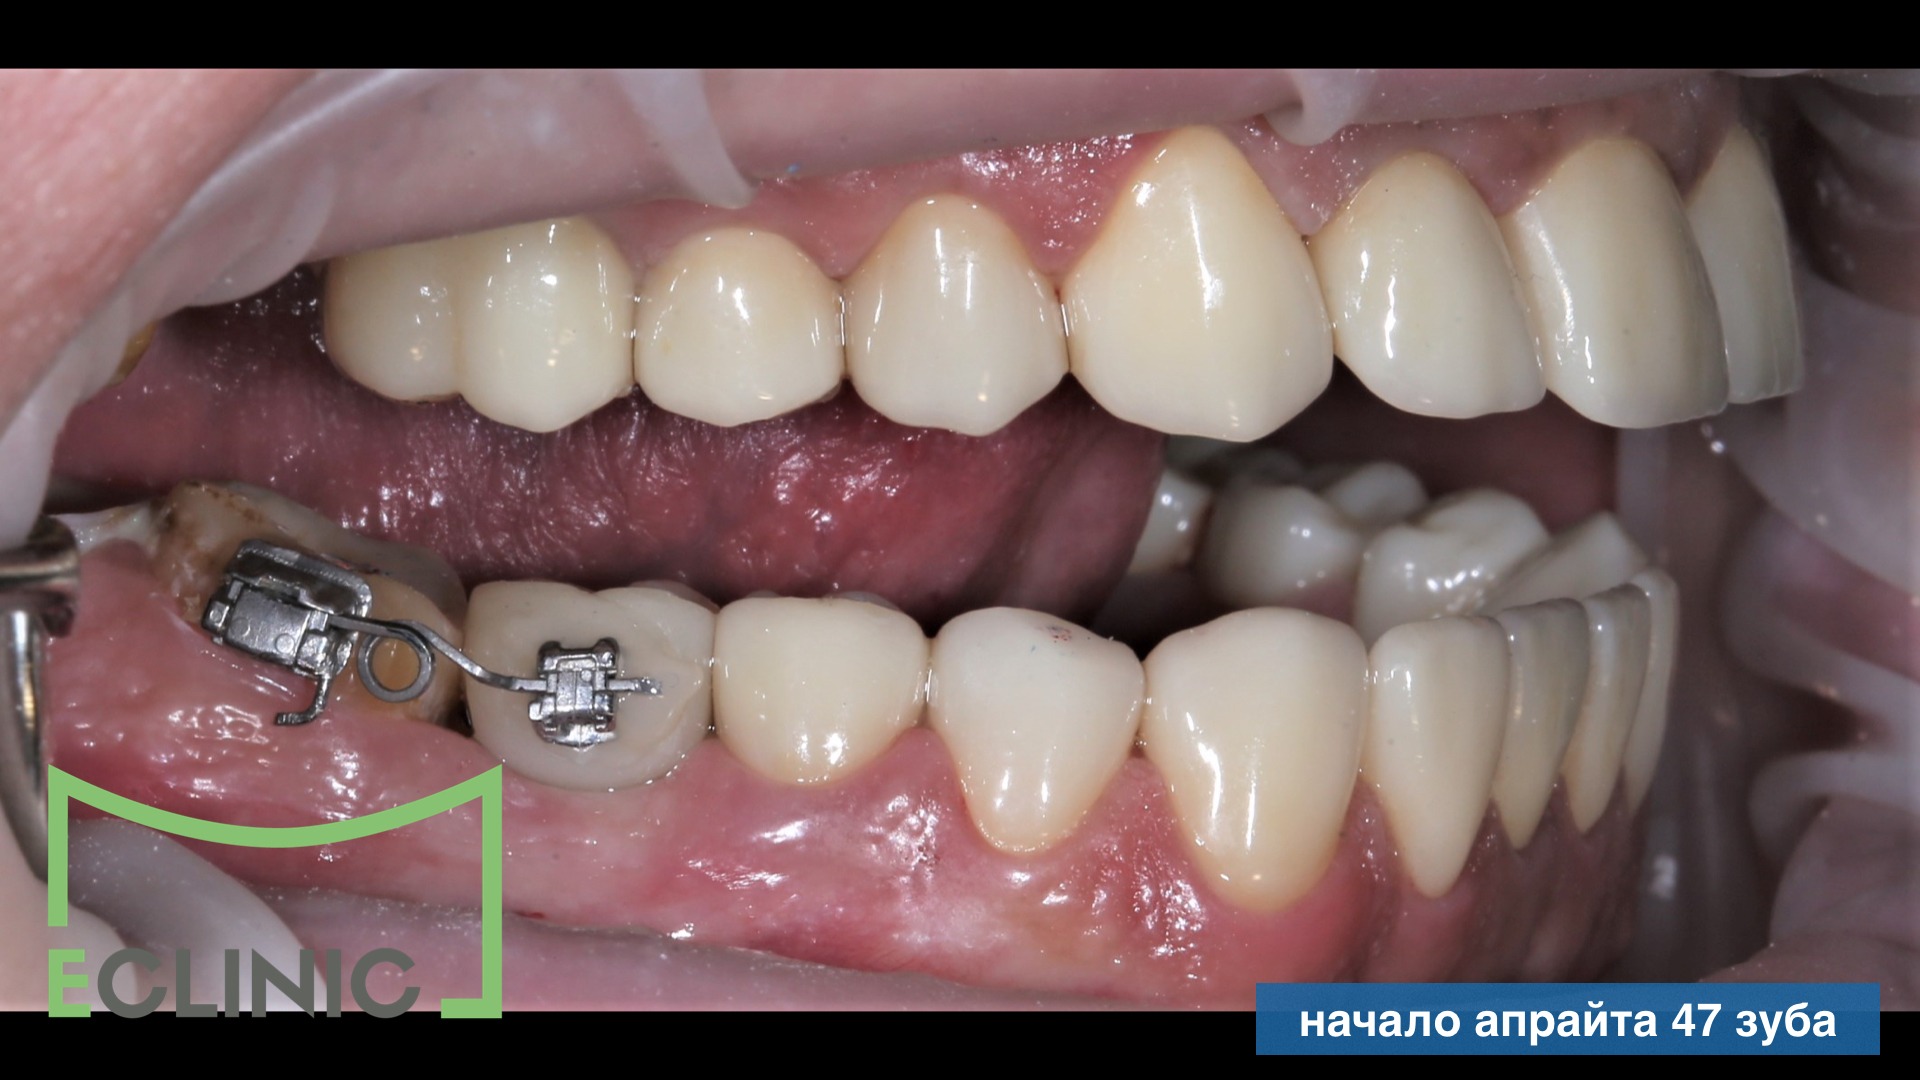

На этапе протезирования мы выяснили что, для трого чтобы сохранить зуб 47 живым, его нужно было на 2 мм внедрить в кость.

Нашим ортодонтом был собрана система для интрузии (внедрения) зуба 47 и, после 3 месяцев, мы завершили протезирование, установив две последние коронки.